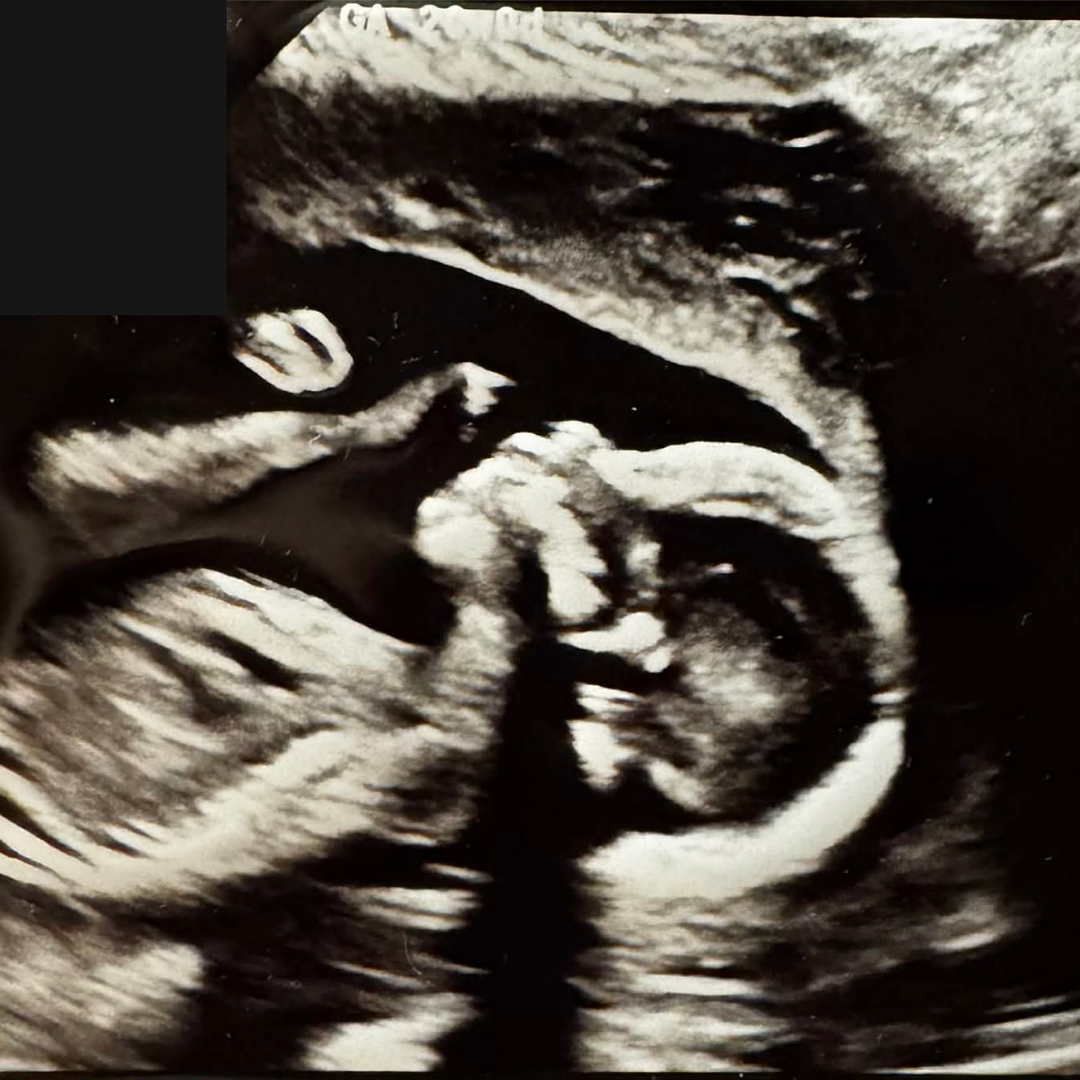

I'm 47 and recently found out I'm gonna be a father again (due date, January 27/26). In order to be there for my child, I made my physical, mental, and emotional well-being a priority. It's important all my boys see me lead by example.